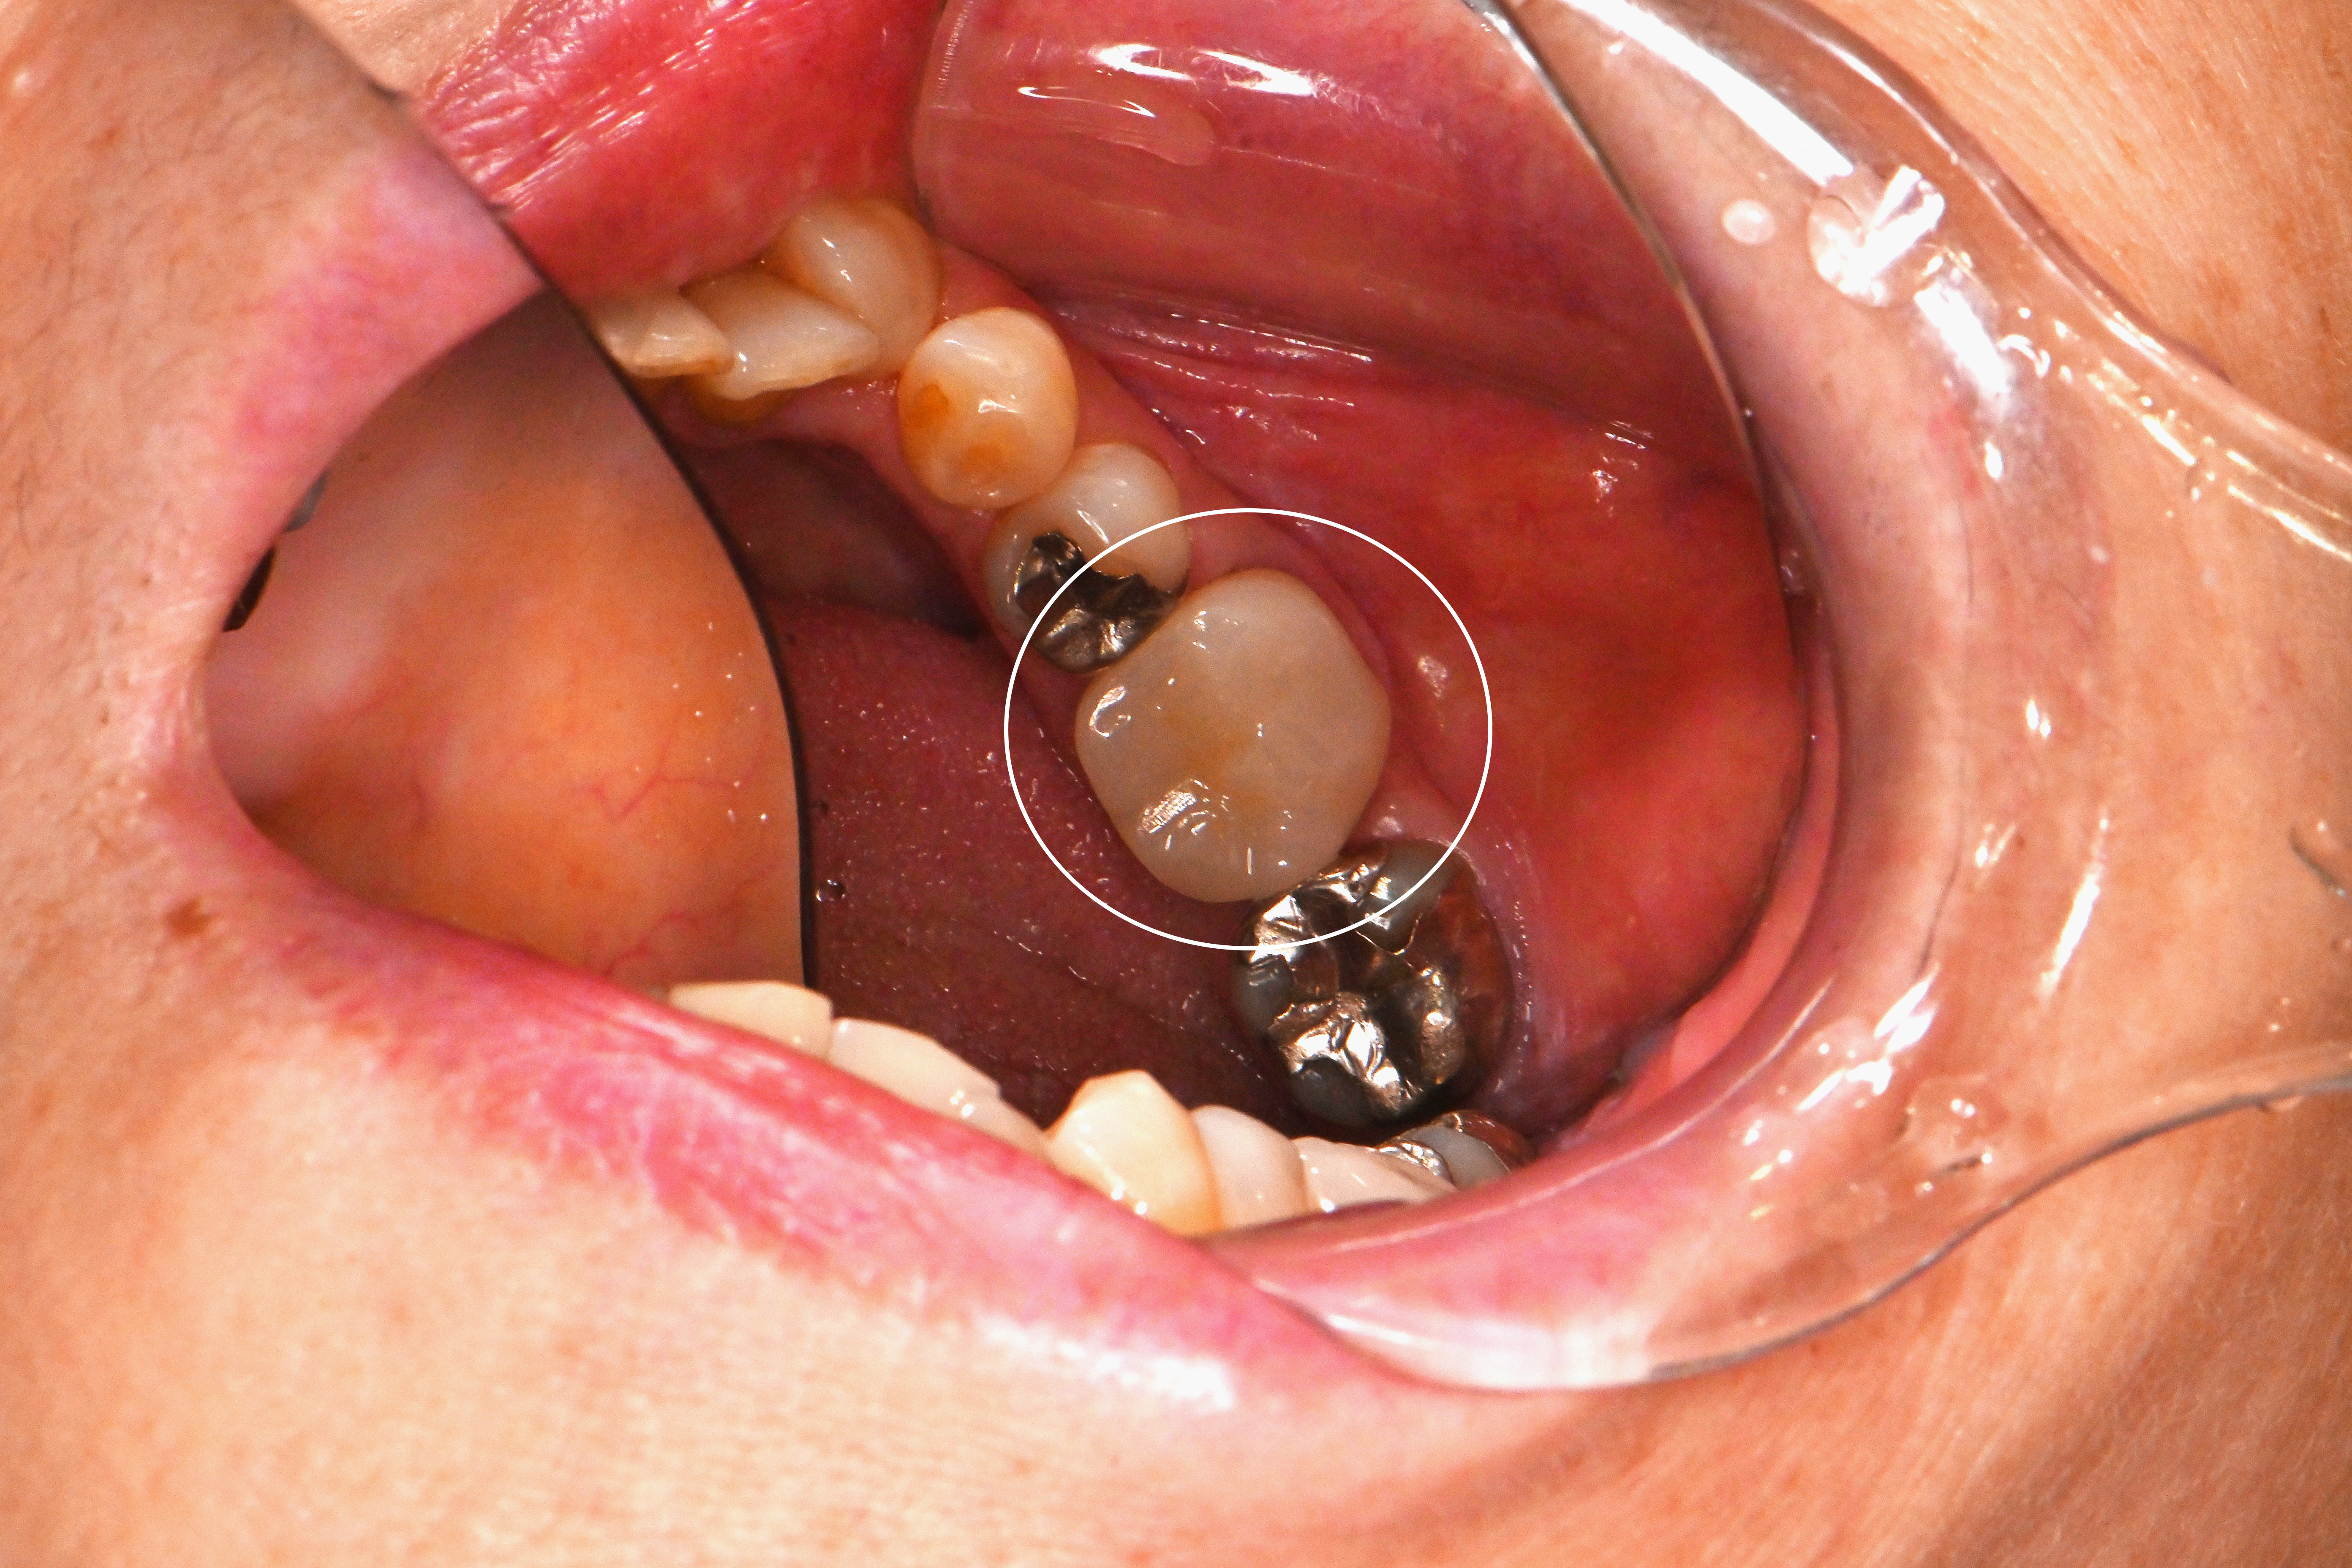

治療前↓

MTAセメントを使用して神経を守る処置を行い、フルジルコニアで修復しました。